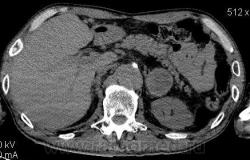

3 - что в голове и печени?

Мне кажется в 6 сегменте печени мтс + еще мтс поражение левого надпочечника вероятнее всего. Мтс в нижние паратрахеальные (с обеих сторон)+бифуркационные л/у. Поражения верхних паратрахеальных не вижу (на коронарах), аксиалы - не показыны сканы выше верхнего края дуги аорты, так что я бы не говорил про поражение верхних медиастинальных лимфоузлов (хотя тут это уже не принципиально) + мтс в головной мозг. А так - центральный рак правого легкого.